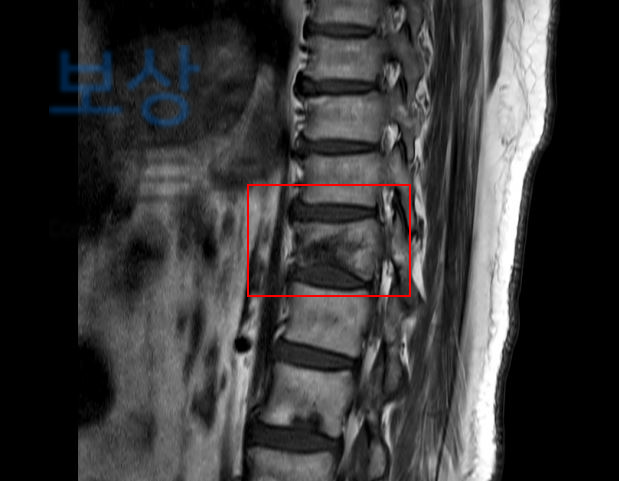

라고 문의해주셨던 김@@님의 실제 보상 사례를 소개해드리겠습니다. 수도권 거주하시는 김@@님께서는 자택에서 발생한 낙상사고로 인해 흉추12번 압박골절 진단을 받으셨습니다.

척추의 골절은 골절 모양의 특성 상 기존 척추의 각도에 영향을 주게 되며

보험 약관에서는 척추 각도의 변형을

장해로 인정하기 때문에 보상받을 수 있는거죠.

보험 약관상 뚜렷한 기형 30%